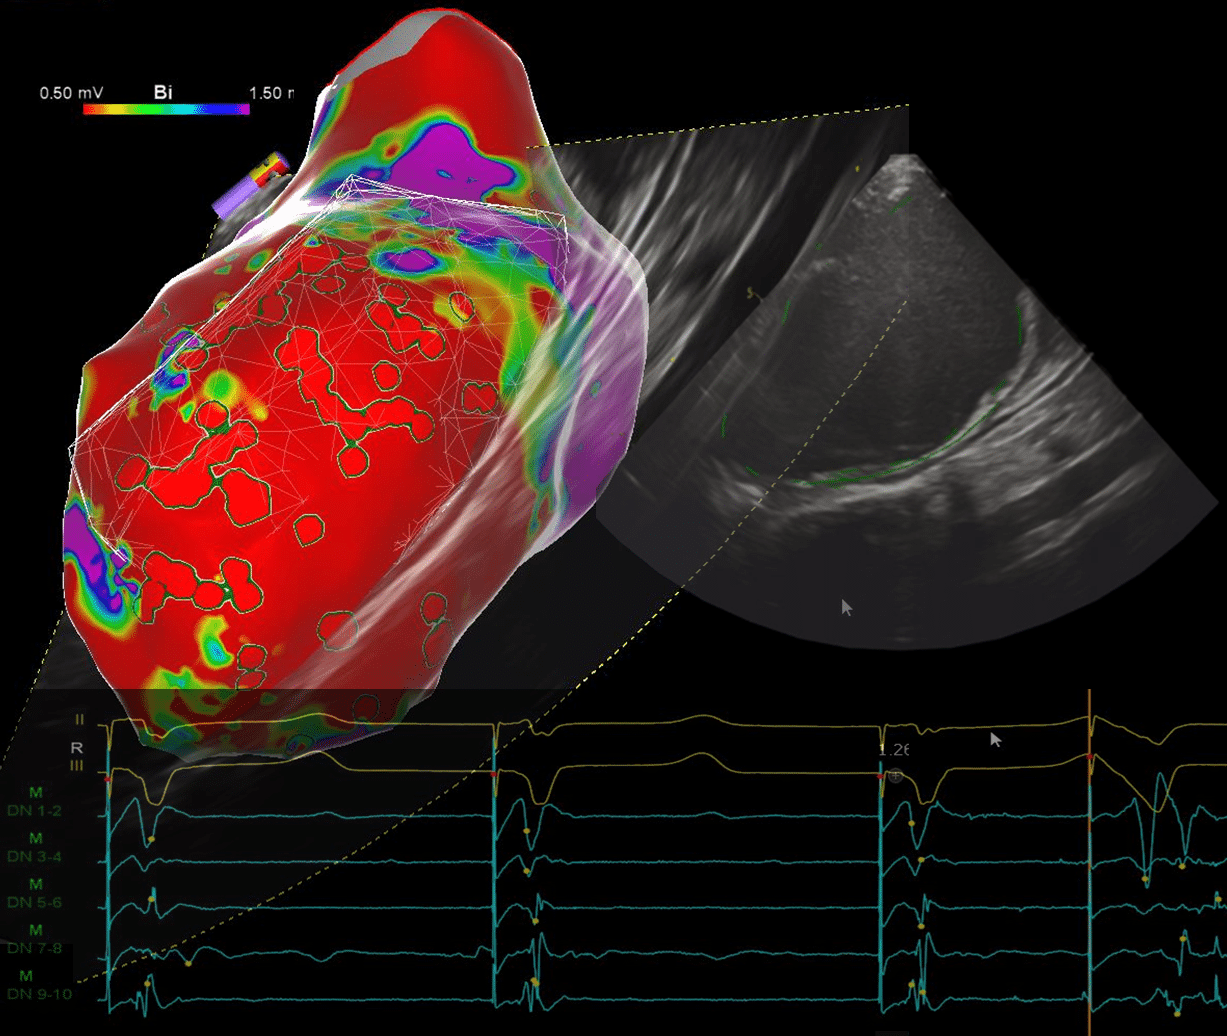

EP in Practice – Program 7: Scar VT

Scar VT is an in-depth look at VT ablation & mapping strategies, It covers:

- Extensive Substrate identification techniques,

- Integration of imaging techniques like ICE and MRI in VT ablation.